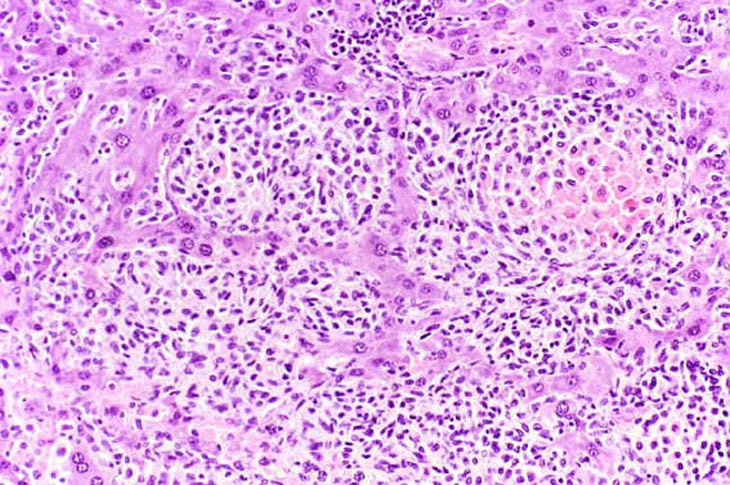

Histiocytic sarcoma (Kupffer cell sarcoma) is a multicentric neoplasm of mice that frequently involves the liver. It is uncertain whether the cells are derived from Kupffer cells or from other histiocytes. The malignant cells grow along the sinusoids and vessels, efface the normal architecture of the hepatic lobules, and sometimes form nodules.

Extensive hepatic involvement by malignant histiocytic cells.

Low and high magnifications of a histiocytic sarcoma with a nodular growth pattern in the liver.

Giant cell formation in a histiocytic sarcoma.